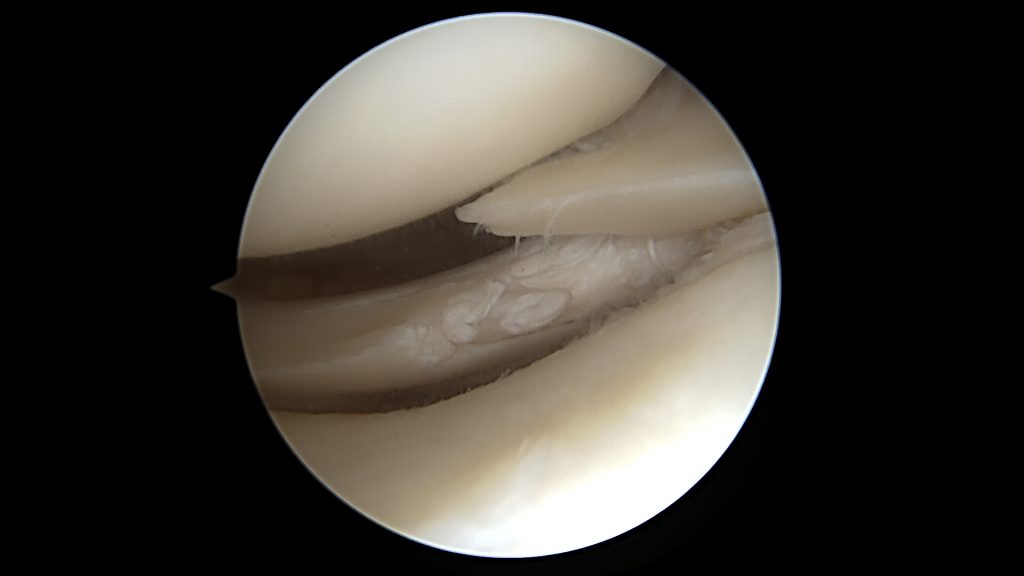

W stawie kolanowym możliwe jest w ten sposób leczenie uszkodzeń łąkotek, chrząstki stawowej, więzadeł krzyżowych, usuwanie ciał wolnych, pobieranie biopsji czy innych. Zabieg przeprowadza się pod kontrolą wzroku przy wykorzystaniu „toru wizyjnego”. Składa się on z układu soczewek zamkniętego w stalowej rurce, który, przez kilku milimetrowe nacięcia skóry oraz torebki stawowej wprowadza się do jamy stawu. W ten sam sposób dostarczamy do stawu światło, którym oświetlamy go od środka. Obraz z soczewek trafia do kamery trzymanej w ręce przez chirurga. Z kamery obraz poprzez przetwornik cyfrowy, obecnie standardem jest obraz 4K, trafia na monitor medyczny przed chirurgiem. Aby wytworzyć przestrzeń w stawie do oglądania go oraz wykonania zabiegu wtłaczana jest do niego, za pomocą pompy, sól fizjologiczna. Przepływ płynu oraz jego ciśnienie jest regulowane automatycznie, w zależności od wielkości oraz specyfiki stawu. Przez drugie niewielkie nacięcie wprowadzamy narzędzia artroskopowe. Podstawowym jest haczyk, którym możemy badać, dotykać oraz poruszać elementami stawu. Do usuwania oraz odcinania uszkodzonych tkanek wykorzystuje się narzędzia manualne typu: punch lub kleszczyki artroskopowe. Stosowane jest także urządzenie mechaniczne typu „shaver”, które ruchem obrotowym specjalnego ostrza odcina uszkodzone fragmenty tkanek oraz usuwa je z jamy stawu na zasadzie zasysania. W przypadku wystąpienia krwawienia stosowany jest elektrokoagulator.